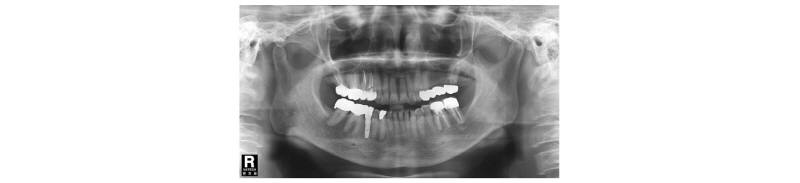

57세의 여성 환자로 기존 브릿지 보철 수복물(#24-27)의 상악 좌측 제 2대구치의 심한 우식으로 인해 내원하여 해당 치아를 발거하였다(Fig. 1). 상악 좌측 제 1 소구치는 근관치료를 시행한 후 보철 수복하기로 하였고 기존 pontic 부위였던 좌측 제 2 소구치와 발거된 제 2 대구치 부위에 #25i, #27i 2개의 임플란트 식립을 통한 브릿지 보철 수복물을 계획하였다(Fig. 2). 기존 pontic으로 유지되었던 좌측 제 2 소구치 부위는 치조제의 심한 수평적 치조골 흡수를 구강 내 임상검사를 통해 확인할 수 있었다. 전층 판막 형성후 상악 좌측 제 2 소구치 부위의 치조정 폭경은 약 2 mm 정도로 측정되었다(Fig. 3, 4). 치조골의 구개측에 약 1 mm의 치조골이 남도록 high speed carbide round bur를 이용하여 치조정에 horizontal intraosseous groove를 형성하였고 협측골의 근심, 원심측에 2개의 vertical intraosseous groove를 형성하였다(Fig. 5). Chisel과 ridge spreader drill (RS kit, Dentium, Korea)을 이용하여 점차적으로 협측 골판을 구개측으로부터 분리시켰다(Fig. 6). Osteotome을 이용, 식립 깊이까지 적용하여 임플란트 식립 부위를 형성하였고 Ø4.3 × 10 mm (Implantium, Dentium, Korea) 임플란트를 식립하였다(Fig. 7). 발치 후 치유된 상악 좌측 제 2 대구치 부위는 상악동 거상술(수직 접근법)을 시행, 골이식을 한 후 4.8 × 10 mm (Implantium, Dentium, Korea)를 식립하였다(Fig. 8). 이후 이종골 이식재(Bio-Oss®, Geistlich, Switzerland)를 식립된 임플란트와 협,구개 측 치조골판 사이의 gap과 협측골판 상방에 적용하고 흡수성 교원질 차폐막(Bio-Gide®, Geistlich, Switzerland)로 피개한 다음 감장절개를 통해 장력없이 봉합하였다(Fig. 9-11). 이후 구강 내 검사 및 방사선 검사를 통해 수술부위 치유상태를 확인하였고 특이한 임상적 소견없이 정상적으로 잘 치유되었다(Fig. 12). 약 3개월 10일 정도의 치유기간 후 이차수술을 시행하였다(Fig. 13). 판막 거상 후 치조제 분할술을 시행하였던 상악 좌측 제 2 소구치 부위에 잘 형성된 신생 골양조직이 관찰되었다(Fig. 14). 상악 좌측 제 2 소구치 부위와 상악 좌측 제 2 구치 부위에 치유지대주를 장착하였고 상악 좌측 제 1 대구치 부위에 추가적으로 임플란트를 1회법으로 식립하였다(Fig. 15). 이차수술 이후 정상적으로 치유가 진행되어 약 2개월 후 최종 보철물 수복을 하였다(Fig. 16, 17). 약 1년 정도의 follow-up시 구강 내 검사와 방사선 검사를 통해서 임플란트 주위 연조직과 변연골이 잘 유지되고 있음을 확인하였다(Fig. 18).

Fig. 1. First visit. Panoramic x-ray view. |